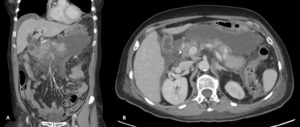

Final follow-up CT imaging, performed 4.5 months after initial presentation, demonstrated only mild irregularity of the left hepatic artery with a small 2 mm fusiform dilatation. There was minimal residual irregularity along the inferior aspect of the common hepatic artery and a small, thick-walled residual fluid collection measuring approximately 1 cm located between the pancreatic neck and stomach. No new vascular abnormalities were identified (figure 5).